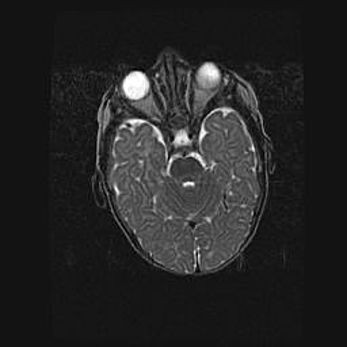

Наружная гидроцефалия с возможной атрофией височных областей.

Возраст: 28 дней

Вес: 3670 г

Пол: мужской

Окружность головы: 38 см

Срок гестации: 40 недель

Гидроцефалия головного мозга у новорожденных – это заболевание, которое характеризуется скоплением избыточного количества спинномозговой жидкости в желудочковой системе головного мозга в результате затруднения её перемещения от места выработки к месту поглощения в кровеносную систему или вследствие нарушения абсорбции. При открытой наружной форме гидроцефалии у новорожденных расширяются и переполняются субарахноидные пространства.

При нормотензивных  формах,  которые,  как  правило,  являются  следствием  перенесенных ишемических  повреждений  паренхимы  мозга,  возможно  сочетание микроцефалии  с нормотензивной гидроцефалией. В основе данных изменений лежит атрофия больших полушарий с преимущественной  локализацией  в  лобно-височных  областях.